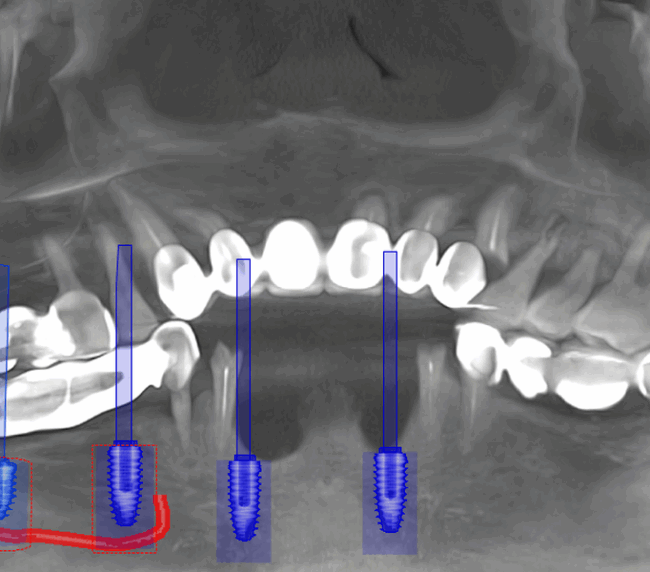

Tomografie (CBCT)

Caz 2